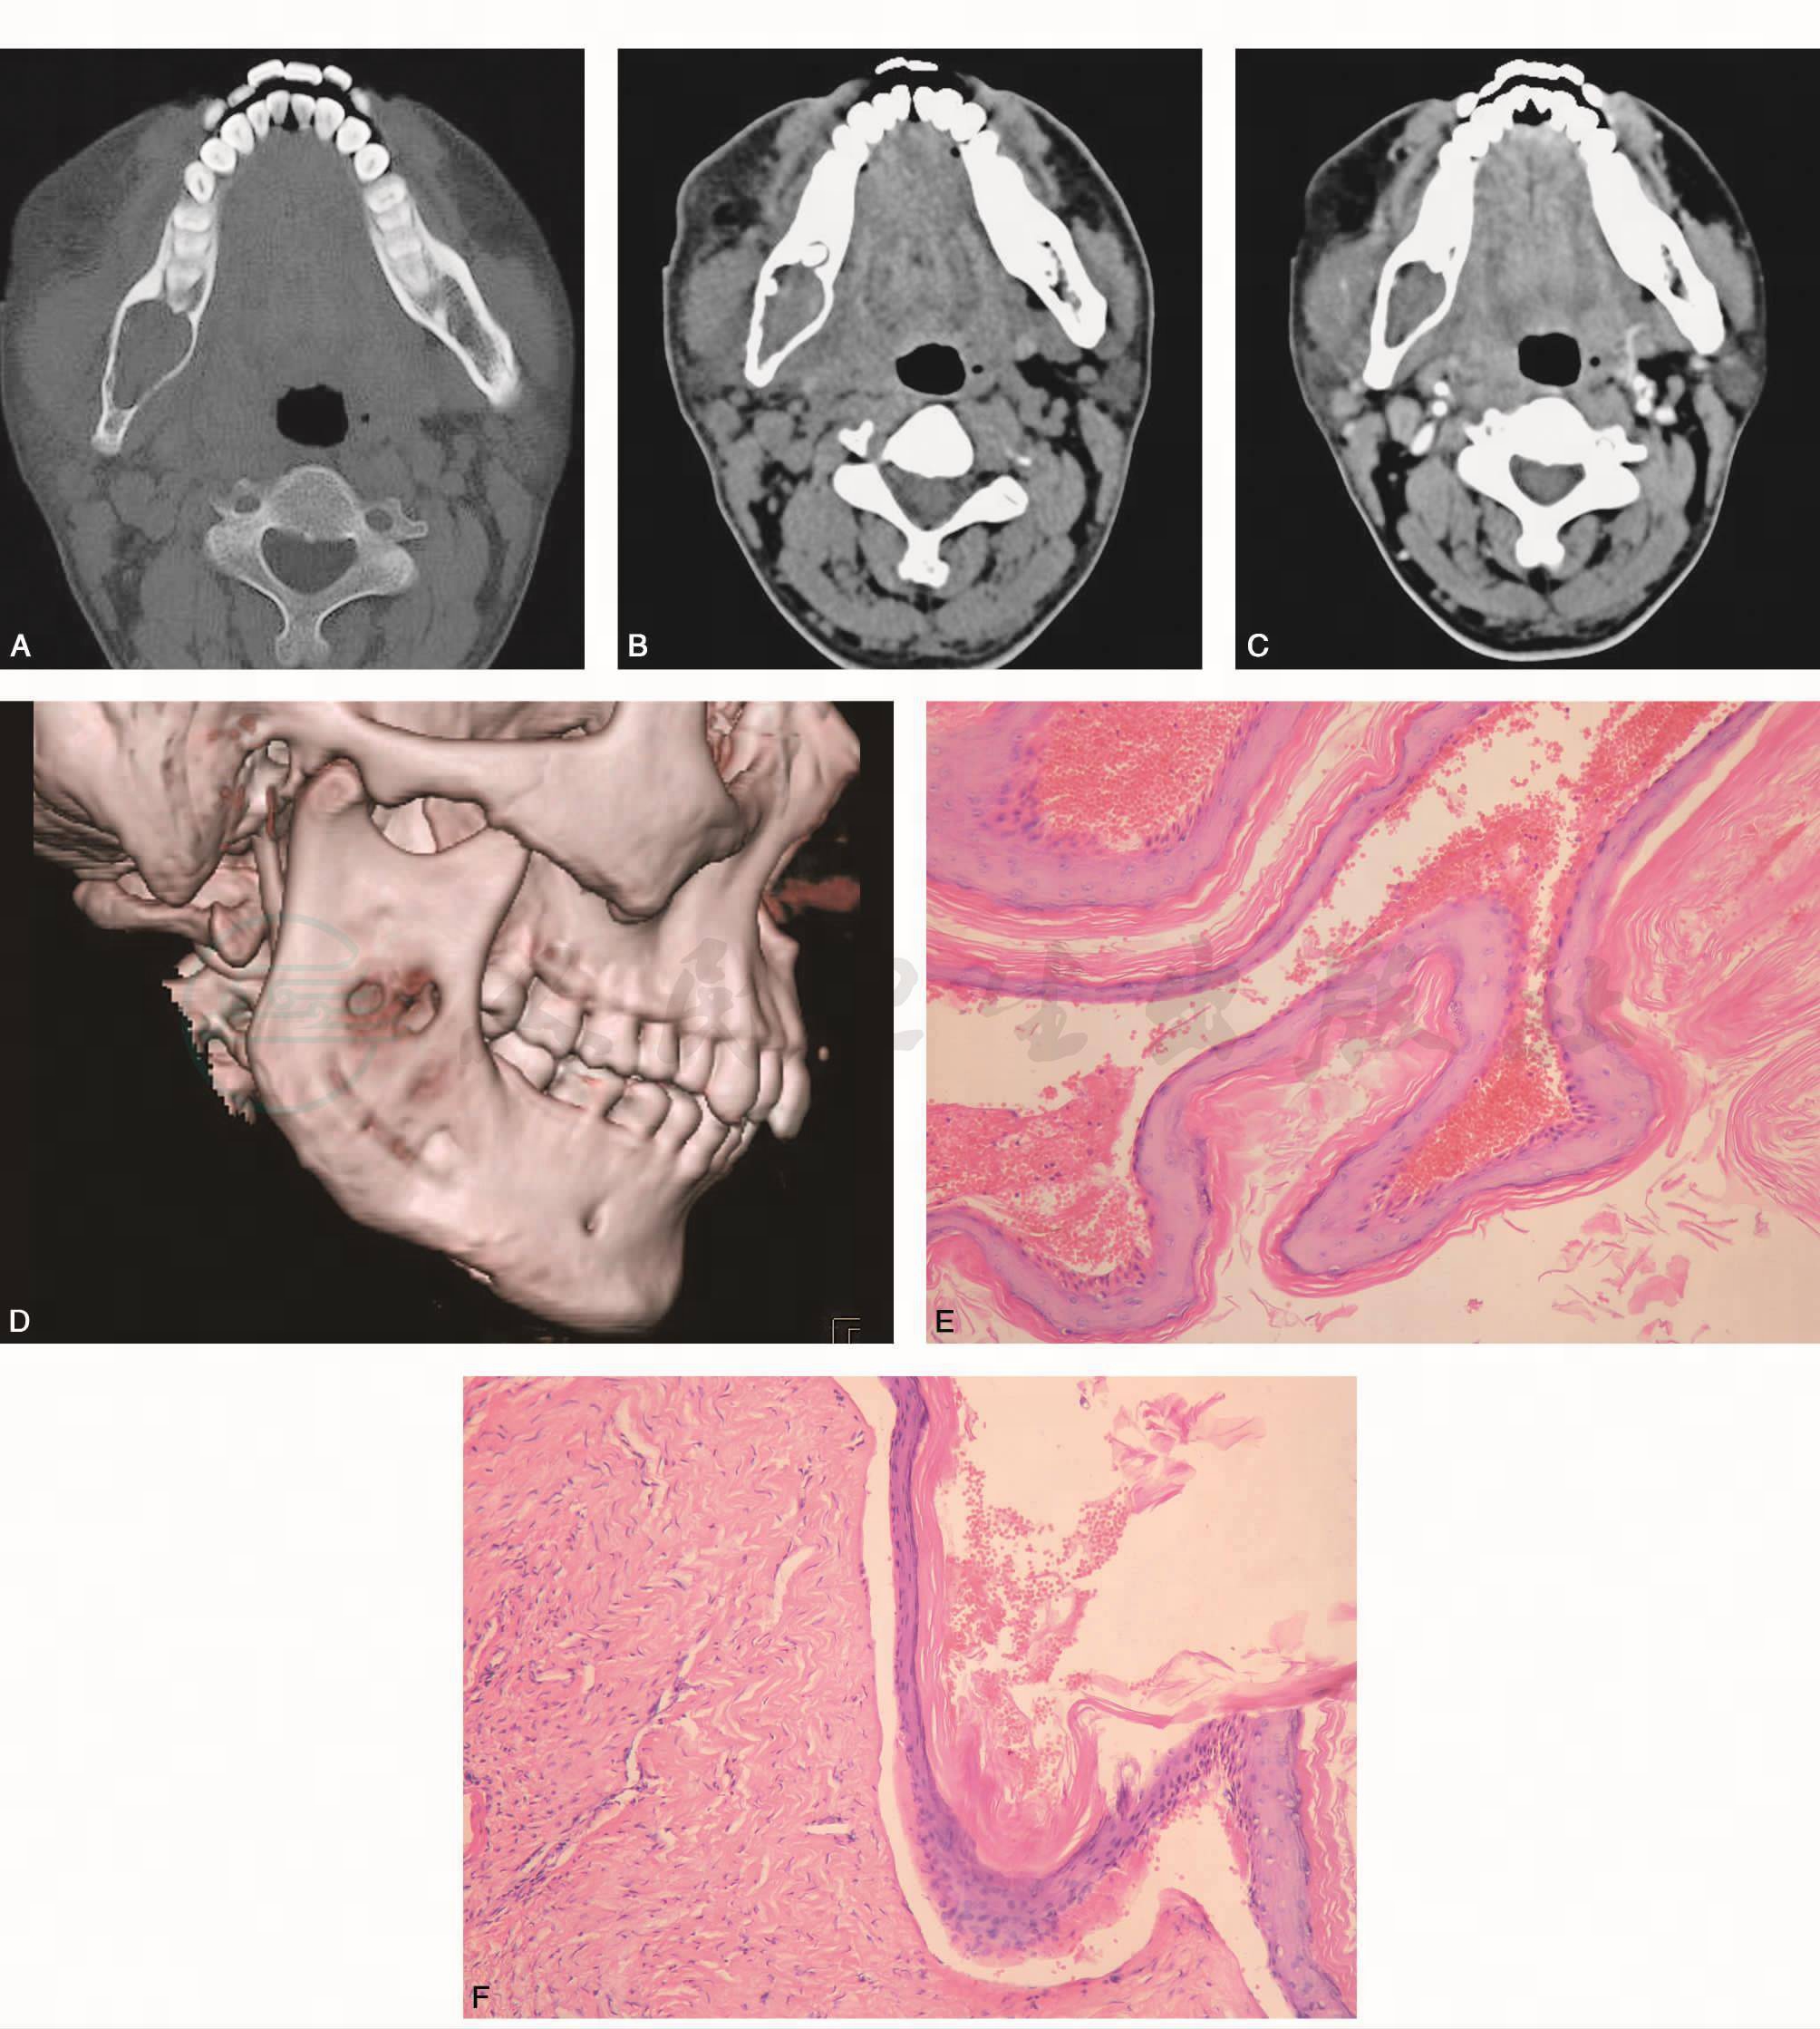

CT(图1A、D)示右下颌骨可见囊状骨质破坏,轻度膨胀,其内可见软组织密度影,周围软组织肿胀。无硬化边、无分隔,囊内无牙胚。影像学诊断:角化囊肿或始基囊肿。

病理诊断(图1E、F):角化囊肿。

图1 颌骨角化囊肿

A. CT骨窗横断位;B. CT软组织窗横断位;C. CT 增强横断位;D.三维重建;E~F. HE×100